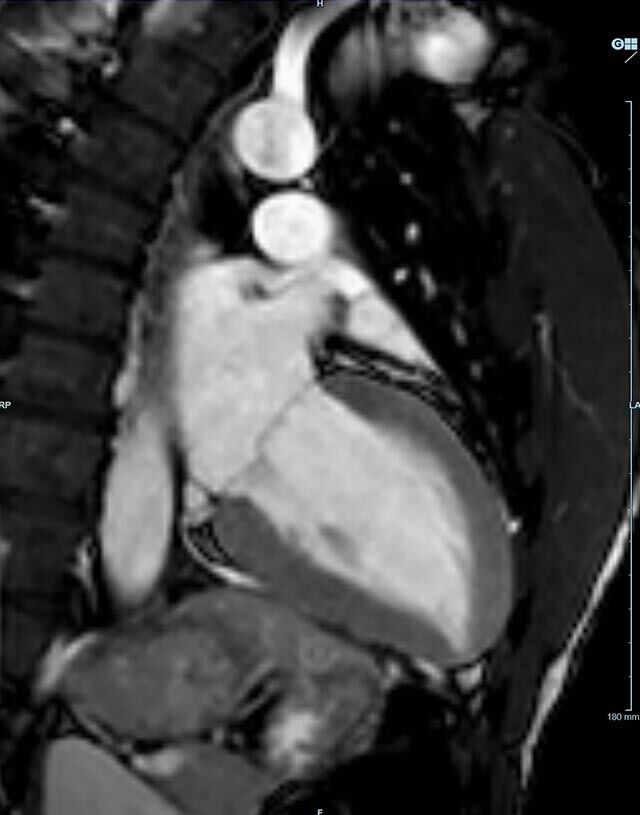

Herz/Thorax

Herz

Durchführung am Standort im Diakonissenkrankenhaus.

• kardiale Ischämiediagnostik mit medikamentöser Stress-MRT (Adenosin)

• Infarktnarbendarstellung/Vitalität

• Kardiomyopathien (z.B. Myokarditis, DCM, HCM/HOCM, Amyloidose, Sarkoidose)

• Klappenbeurteilung mit Phasenkontrastangiographie

• Tumoren Herz und Mediastinum

• Fehlbildungen

• MR-Angiographie zur Erfassung und Verlaufskontrolle von Aneurysmen der Aorta thorakalis und ihrer Gefäßabgänge